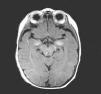

El electroencefalograma muestra actividad delta persistente temporo-occipital derecha y la resonancia magnética, lesiones hiperintensas en regiones parietales y regiones temporales mediales de predominio izquierdo compatibles con melanosis cortical (fig. 2). Los demás estudios son normales.

La melanosis neurocutánea se asocia a nevus pigmentados múltiples o de gran tamaño que suelen localizarse en la convexidad y base del encéfalo, en el puente o el bulbo3 pero en nuestra paciente se presentaron lesiones múltiples en regiones parietales y temporales mediales.

Para un diagnóstico adecuado se requiere resonancia magnética para detectar, como en esta paciente, las alteraciones compatibles con melanosis del SNC. El electroencefalograma muestra anormalidades locales en región temporal y occipital tal como está descrito en la literatura. Cuando se hace citología de líquido cefalorraquídeo se pueden encontrar los gránulos de melanina con tinción de Mason-Fontana8,10.